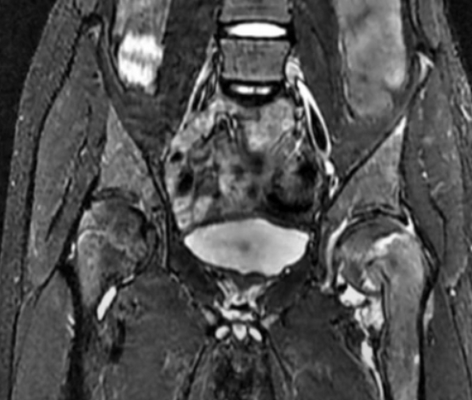

Аваскулярный некроз головки бедра.

Вид указанной патологии на МРТ, изменения соответствуют 2 стадии

К развитию аваскулярного некроза приводит длительное нарушение питания тазобедренного сустава на фоне загустевания крови, тромбообразования, сдавления, скручивания сосудов. В костной ткани при ишемии создаются пустоты, приводящие к деформации, отслойке хряща. Клинические проявления неспецифичны, что вызывает трудности в постановке диагноза. Провоцирующих факторов множество:

воздействие ионизирующего облучения и пр.

Ранние изменения не видны при рентгенографии, ультразвуковом исследовании. МРТ тазобедренного сустава - один из эффективных способов определить болезнь на начальной стадии.